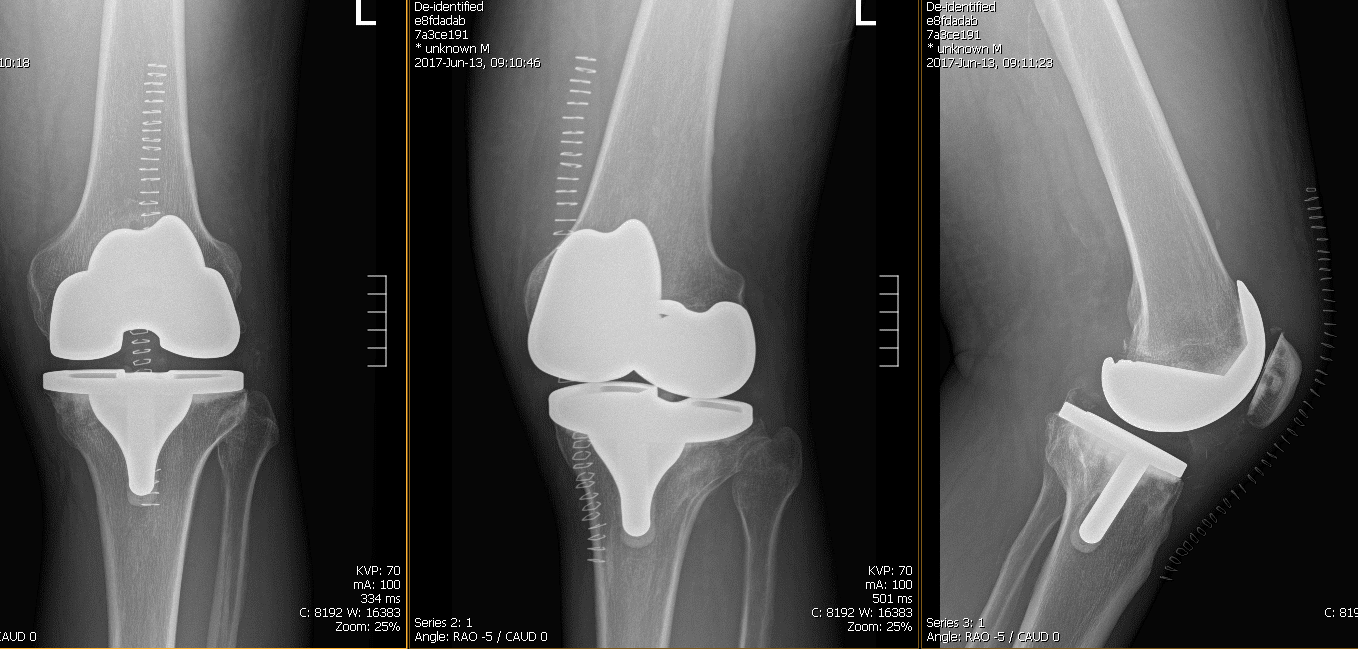

Postoperative films revealed Distal femur, patella, proximal tibia and proximal fibula demonstrate intact cortical margins with no acute fracture. His wound was inspected, clear no signs of infection.Staples removed.